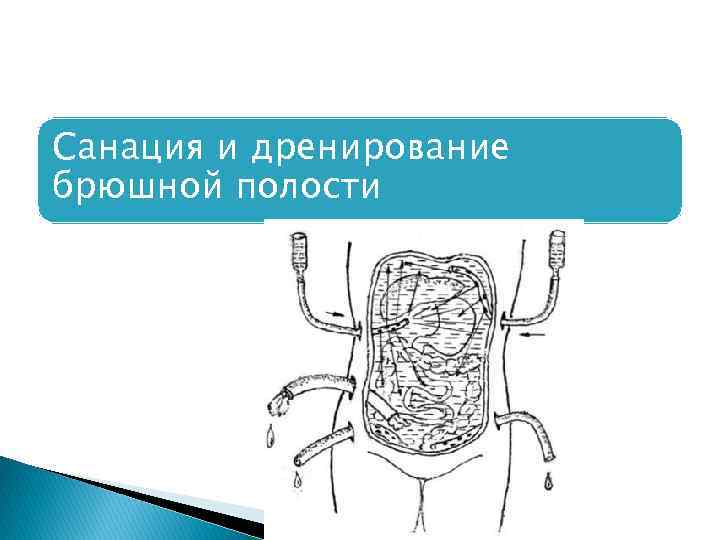

Санация и дренирование брюшной полости

Санация и дренирование брюшной полости